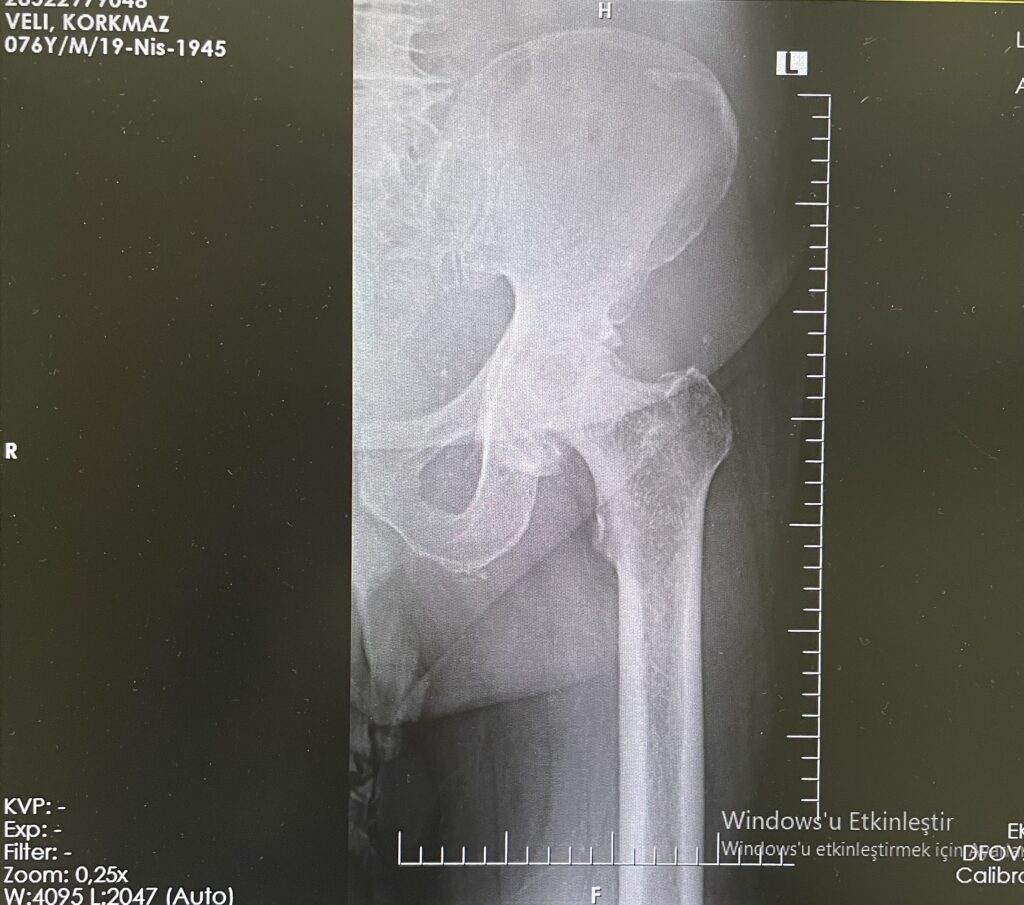

V.K.